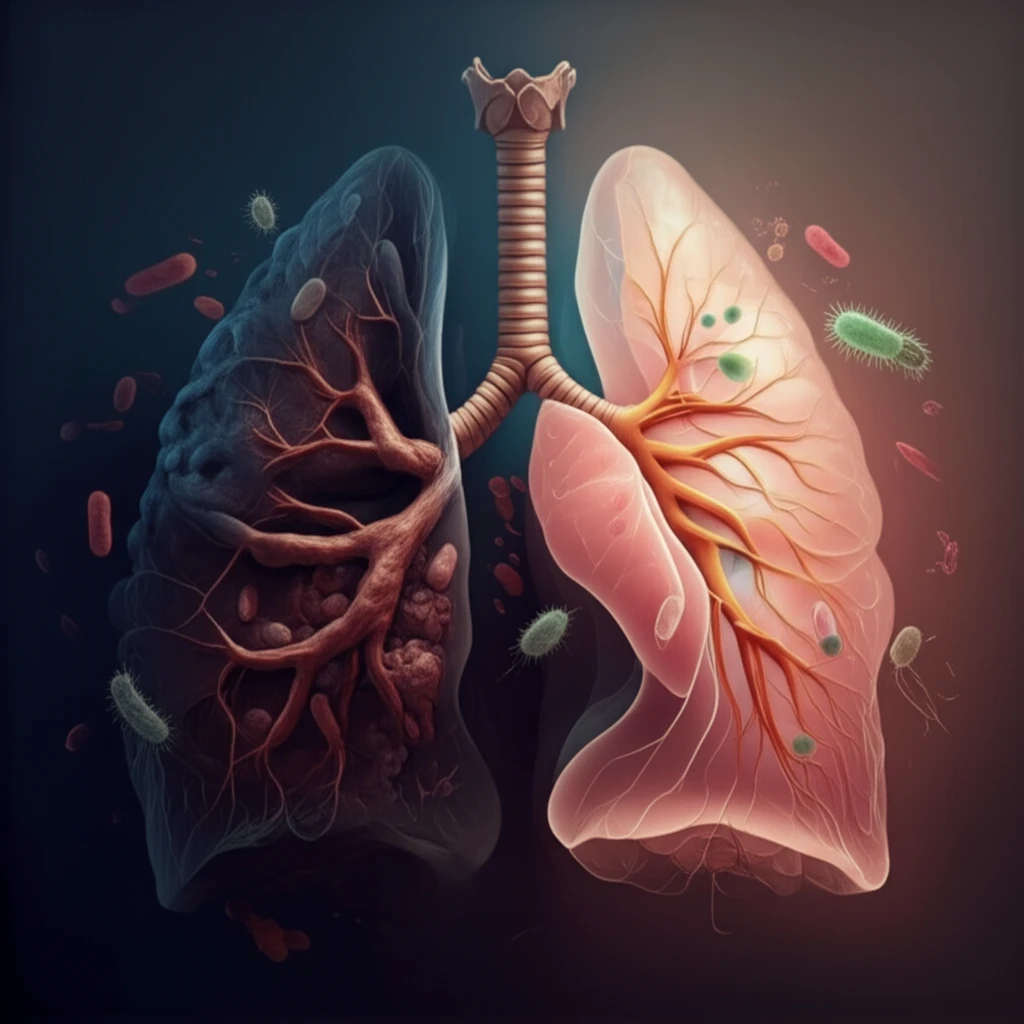

Imagine battling a serious illness, only for it to vanish without a trace. That's the reality of spontaneous regression (SR), a rare and intriguing phenomenon where cancer disappears without medical intervention. While SR is uncommon, especially in aggressive cancers like small cell lung carcinoma (SCLC), understanding its mechanisms could revolutionize cancer treatment.

SCLC is a particularly aggressive form of lung cancer, often diagnosed at advanced stages. Traditional treatments involve chemotherapy, radiation, and surgery. However, in extremely rare cases, something unexpected happens: the cancer simply goes away on its own. This is spontaneous regression, and scientists are keen to understand why it occurs.

Researchers are actively investigating potential explanations for SR in SCLC, including immune system activation and changes in the tumor environment. This article will explore a fascinating case where SCLC regression occurred alongside a bacterial infection, offering a glimpse into the complex interplay between infection, immunity, and cancer.

- Immune System Activation: The bacterial infection may have triggered an immune response that inadvertently targeted the cancer cells.